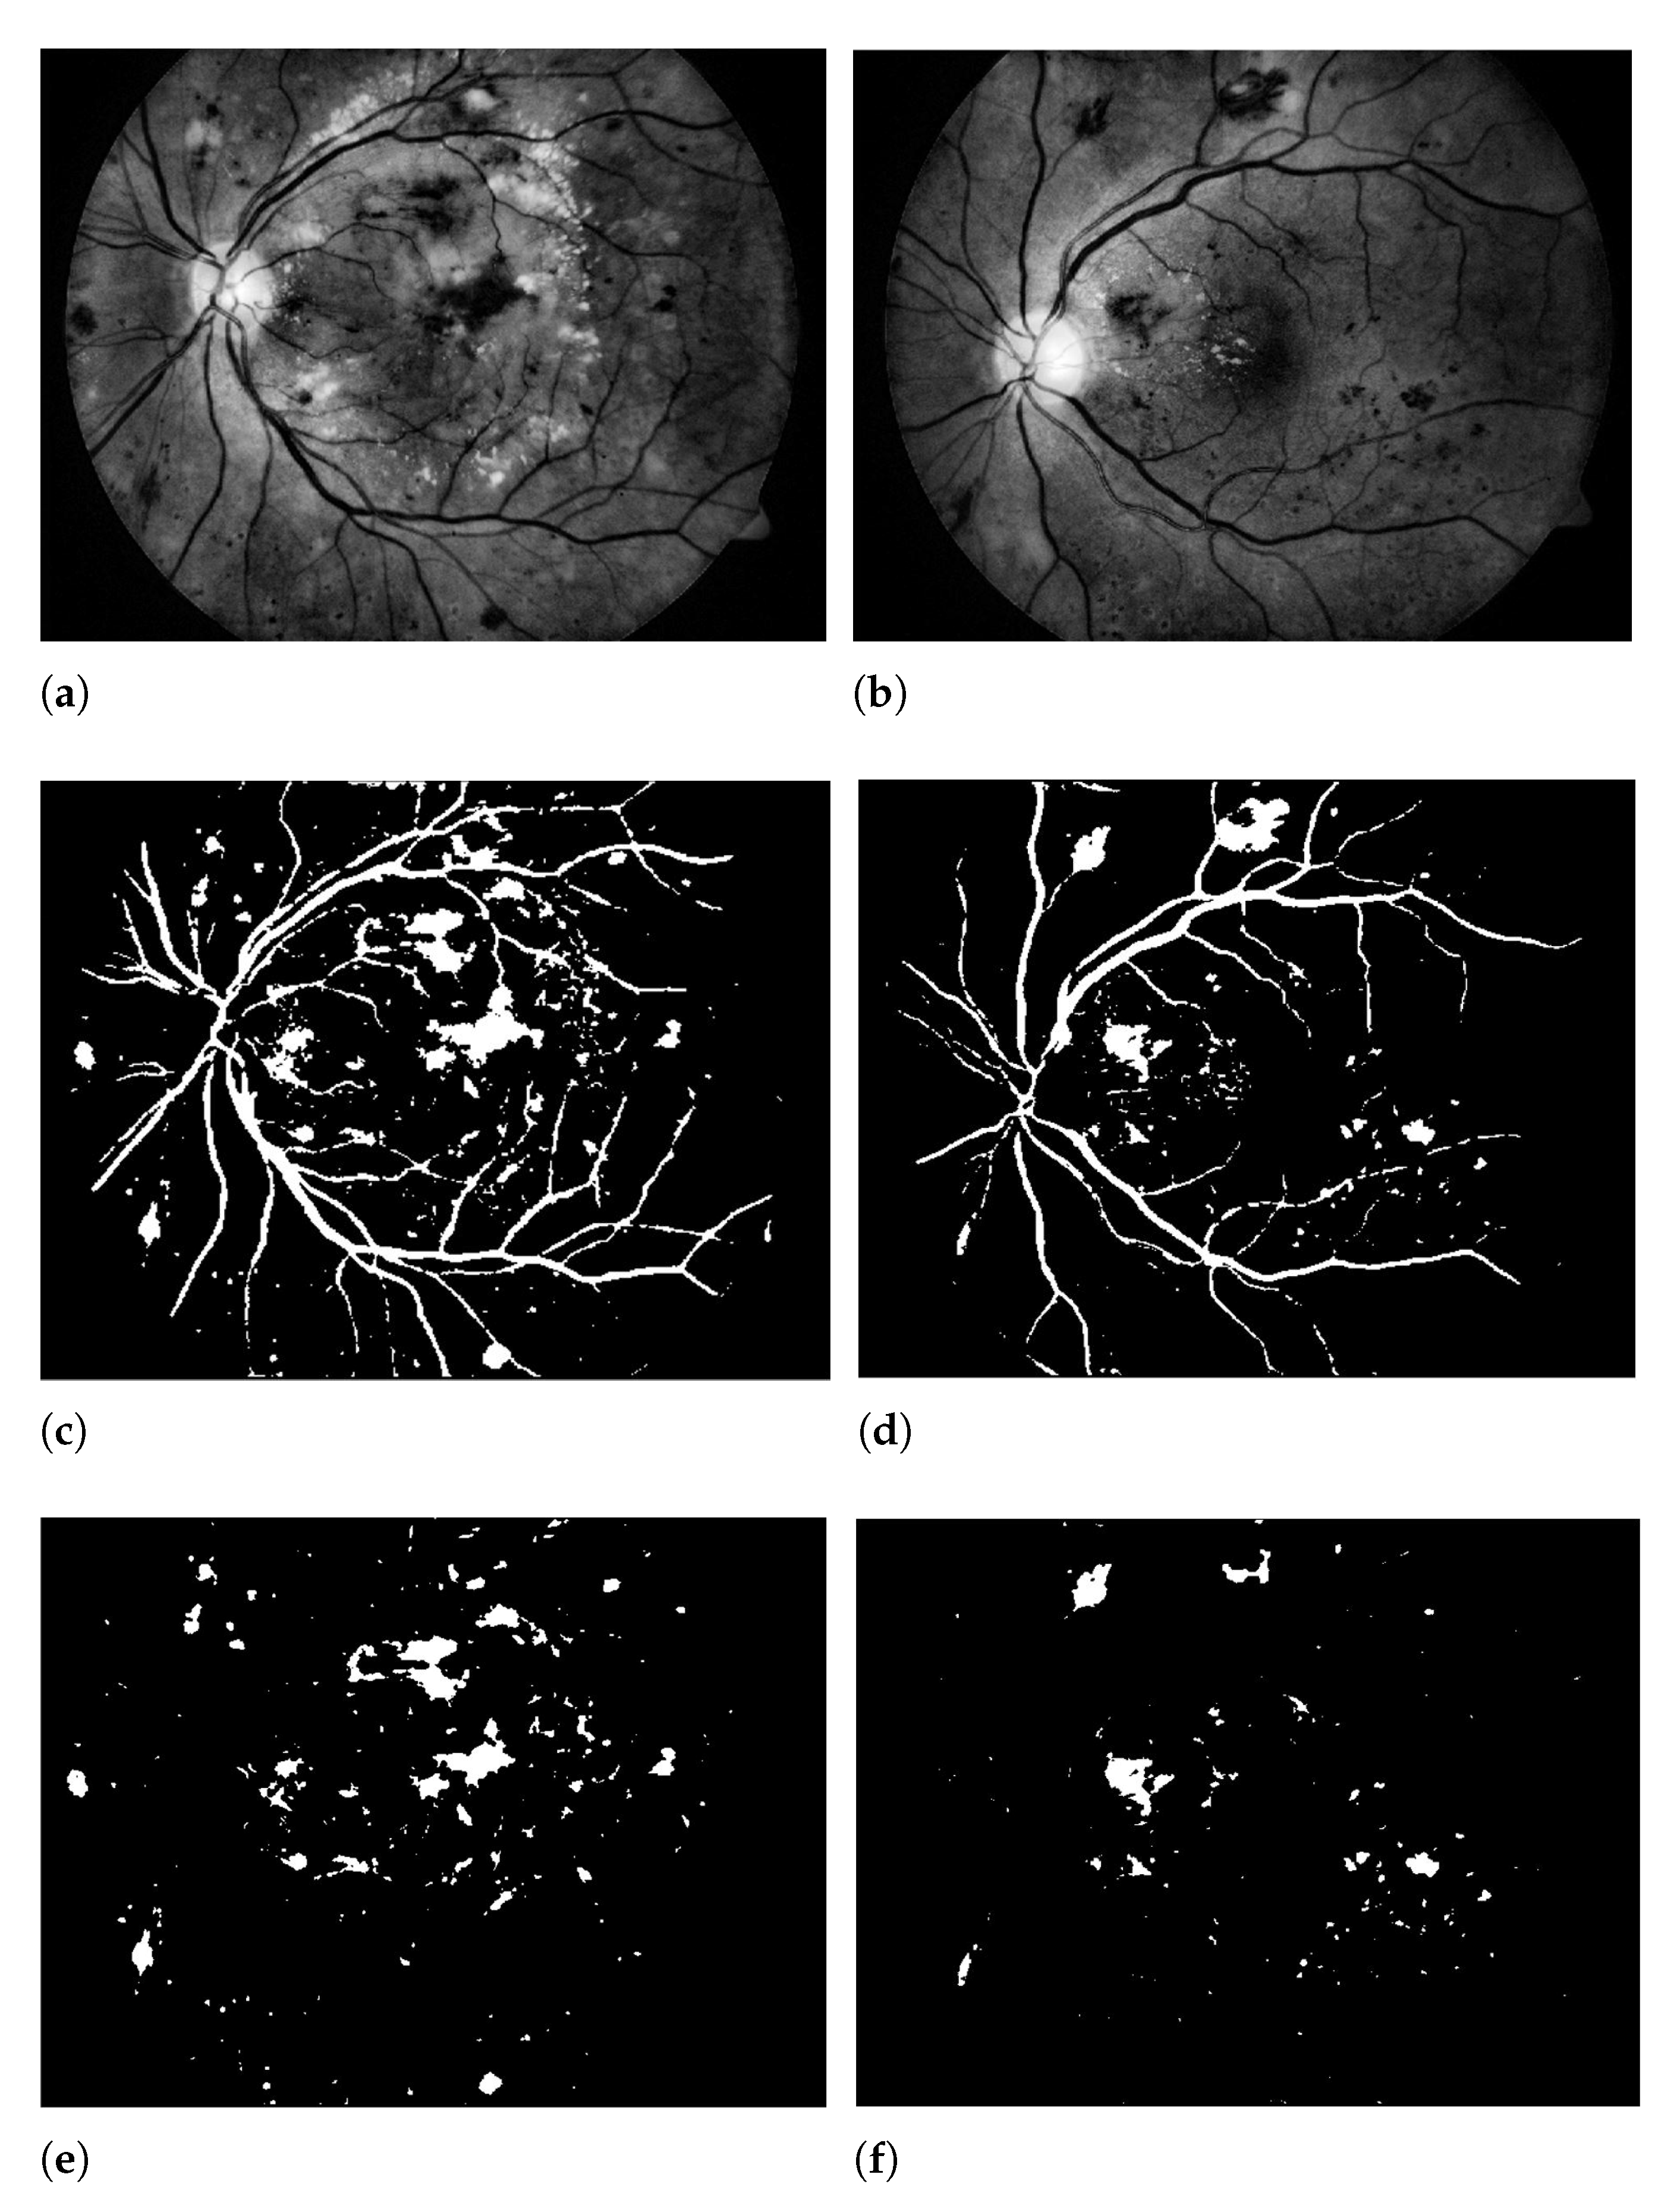

Afterwards, a max-pooling layer is down sampled in CNN layers that reduces the spatial size of the feature map. In our proposed work, two max-pooling layers are created to reduce the features dimension and remove redundant spatial information as displayed in Figure 6.

Figure 6.

The retinal fundus image. (a,b) Proposed modification to contrast enhanced images, (c,d) Background estimated results using OTSU method corresponding to the 1st row, (e,f) Proposed 3D-CNN segmentation results corresponding to the 1st row, (g,h) Extraction of hemorrhages corresponding to the 1st row.

The trained CNN is registered as a new network and used in the testing method. The final achieved results are then improved using morphological operations (opening and closing). Figure displayed the obtained results of segmentation by using our proposed technique.